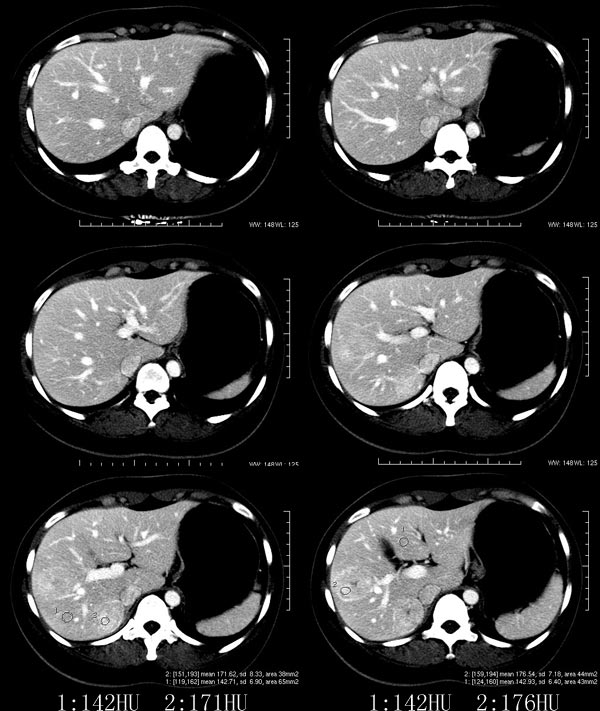

以下是引用52yingxiang在2007-9-16 10:16:00的发言:[br]肝脏局灶性结节增生影象表现(fnh)[br][br]肝脏局灶性结节增生是一种少见的肝脏良性肿瘤,可表现为边界清楚并无包膜的实质性肿块。病变大小不一,多系单发,亦可多发。组织学上是由结构紊乱的肝细胞、库普弗细胞、胆管、血管和粗厚的纤维性间隔所组成。[br]局灶性结节增生的ct表现可归纳为6点:[br]1、密度变化是其特征性改变,平扫多为低密度,少数为等密度,无论增强的早期或晚期均可能呈等密度,增强扫描有助于发现平扫为等密度的病灶;[br]2、中心疤痕,部分病灶在动态ct扫描时早期可看到中心疤痕增生性结节性病灶,ct血管造影也可看到普通ct不能显示的车轮状血管和车轴样改变;[br]3、纤维性分隔影,平扫为低密度,增强后为高密度;[br]4、包膜征象,增强后可以出现包膜强化,晚期较明显;[br]5、邻近血管的改变,主要是肝静脉受压,是发现等密度病变的重要依据;[br]6、瘤内胆管显影,这需要在胆管造影增强的情况下方能显示,出现率不高。[br][br]本例特点: 平扫低密度,增强动脉期明显强化,中心点条状低密度影(考虑纤维瘢痕),静脉期及延时期明显退减并与肝呈等密度,但中心仍可见低密度灶。[br]考虑肝脏局灶性结节增生(fnh)